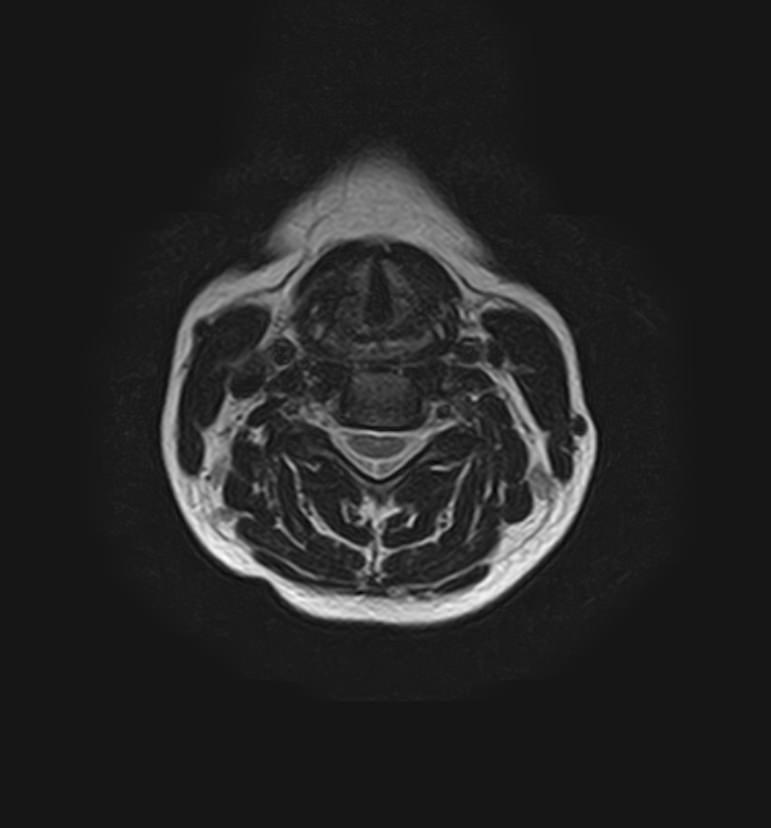

Для того, чтобы оценить состояние шейных позвонков с прилегающими тканями и одновременно визуализировать плечевой сустав, в нашей клинике выполняется комплексное обследование, включающее два протокола: МРТ шейного отдела позвоночника и МРТ плечевого сустава.

Метод МРТ позволяет оценить состояние всех анатомических областей шейного отдела позвоночника: костную структуру позвонков, спинной мозг с отходящими от него нервными корешками и окружающие мягкие ткани. Протокол обследования плечевого сустава включает оценку костной структуры, суставной капсулы, полости сустава с выстилающей его синовиальной оболочкой, связок, сухожилий, мышц и окружающих мягких тканей.